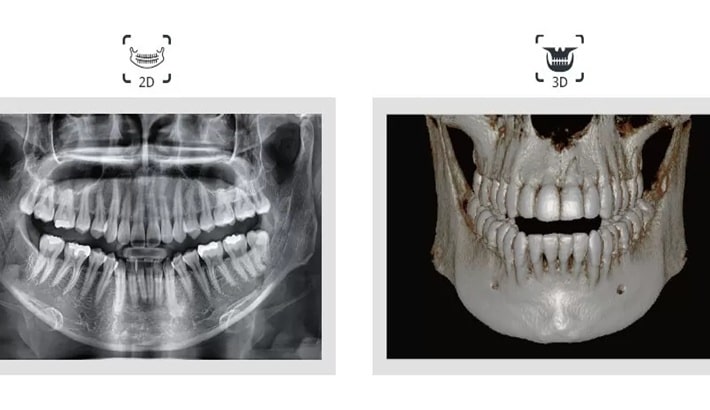

تفاوت عکس opg شیراز با سیتیاسکن دندان (کدام یک برای شما مناسبتر است؟)

وقتی فرد با درد دندان، نیاز به ایمپلنت، احتمال عفونت یا مشکلات مفصل فک به دندانپزشک مراجعه میکند؛ معمولاً اولین توصیه تهیه یک تصویر تشخیصی است. در شیراز، بیماران اغلب بین دو روش پرتکرار یعنی عکس OPG شیراز و سیتیاسکن دندان دچار تردید میشوند؛ زیرا تصور میکنند هردو یک هدف را دنبال میکنند. در حالیکه این دو روش تفاوتهای اساسی از نظر دقت، کاربرد، هزینه، سرعت و میزان اشعه دارند؛ همچنین انتخاب بین آنها باید بر اساس شرایط بیمار انجام شود. عکس opg شیراز تصویری دوبعدی و گسترده از فک، ریشهها، سینوسها و دندانها ارائه میدهد و برای بررسی اولیه بهترین انتخاب است. اما سیتیاسکن دندان، بهویژه CBCT، یک تصویر سهبعدی با جزئیات بسیار بالا تولید میکند؛ این نوع تصویربرداری برای تصمیمگیریهای حساس مانند جراحی، ایمپلنت یا بررسی شکستگیهای ظریف ضروری است. مرکز تابا این امکان را فراهم کردهاند که بیمار دقیقاً همان روشی را انجام دهد که براساس تشخیص پزشک برایش مناسبتر است.

عکس OPG شیراز تصویری دوبعدی و وسیع از هر دو فک ارائه میدهد. این تصویر برای ارزیابی کلی وضعیت دهان، تشخیص دندانهای نهفته، بررسی شکل فک، تحلیل سینوسها و مشاهده ریشه دندانها مناسب است. گرچه OPG نمیتواند عمق و ضخامت استخوان را مانند تصاویر سهبعدی نشان دهد، اما برای شروع مسیر درمان بسیار ارزشمند است؛ زیرا دندانپزشک در یک نگاه میتواند تمامی ساختارهای مهم دهان را ارزیابی کرده و مشکلات اولیه را شناسایی کند. یکی از دلایل محبوبیت عکس OPG در شیراز ، هزینه پایین، سرعت بالا و مقدار بسیار کم اشعه آن است. به همین دلیل، بسیاری از پزشکان در اولین مراجعه بیمار، قبل از درخواست روشهای دقیقتر، تهیه OPG را لازم میدانند.

تصویر سهبعدی سیتیاسکن؛ انتخاب مناسب برای درمانهای حساس و پیچیده

سیتیاسکن دندان یا CBCT تصویری سهبعدی تولید میکند که شامل حجم، عمق، تراکم استخوان و موقعیت دقیق ساختارهاست. این تصویر به دندانپزشکان اجازه میدهد کوچکترین جزئیات را بررسی کنند، چیزی که در OPG قابل مشاهده نیست. در مواردی مانند برنامهریزی برای کاشت ایمپلنت، تعیین محل دقیق عصب فک و تشخیص کیستهای پیچیده تنها CBCT اطلاعات لازم را فراهم میکند. این روش اشعه بیشتری نسبت به OPG دارد و هزینه آن نیز بالاتر است، اما ارزش آن در روشهای درمانی حساس بسیار بالا است. مرکز تصویربرداری پزشکی تابا در شیراز از دستگاههای CBCT نسل جدید استفاده میکند تا تصویرها با کمترین خطا و دقیقترین جزئیات ثبت شود.